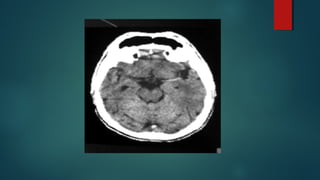

Este documento es el programa para un taller de imágenes del curso de emergencia 2015 impartido por el Dr. Víctor Delgado. El taller se centra en el uso de imágenes médicas para el diagnóstico y tratamiento de pacientes en coma traumático según la base de datos de Marshall. El Dr. Delgado es el único instructor repetido a lo largo del documento.